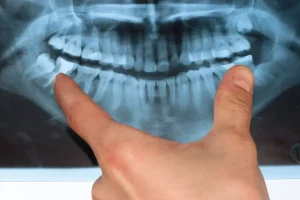

Dental implants are implants that are very compatible with human physiology and are implanted into the alveolar bone, so that the rest of the implants